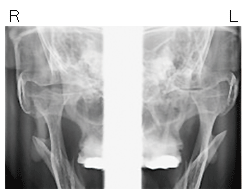

図❷ TMJパノラマ断層写真

画像所見:67にインレー処置が施行されているものの、根尖に透過像は認めなかった(図❶~❸)。